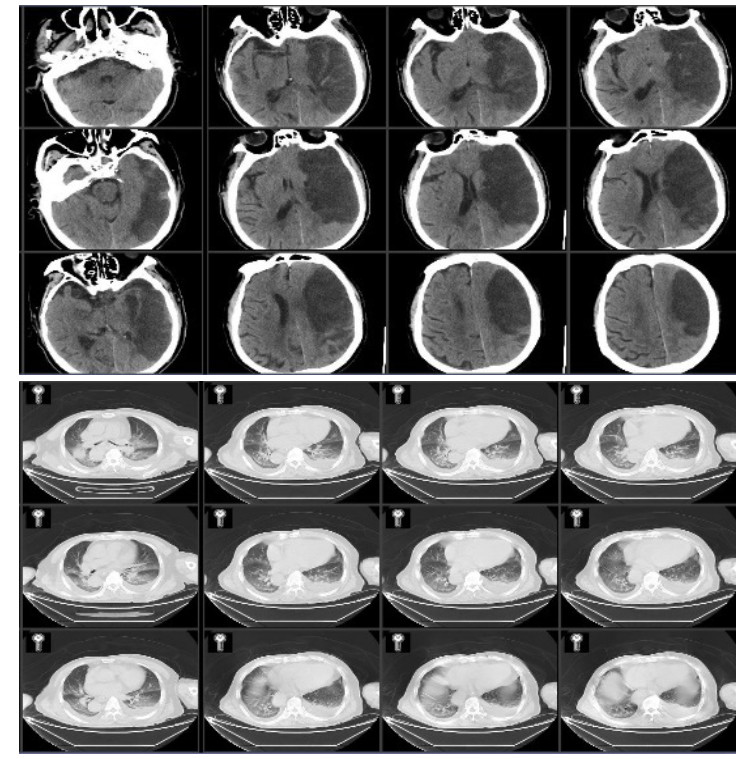

病例2,男性,80岁,因“突发右侧肢体无力1周,加重伴意识障碍1 d”由外院转入我院。外院头颅CT示左侧额颞叶片状低密度灶,诊断大面积脑梗死。头颅CTA示左侧颈内动脉及大脑中动脉部分闭塞,急诊溶栓治疗无效。既往有高血压病史20年,无冠心病房颤病史。入院查体:生命体征平稳,体温37.8 ℃,GCS 2-5-1,双瞳等大等圆,光敏,左侧肢体有不自主活动,右侧肢体无活动,右侧巴氏征阳性。入院诊断为左额颞大面脑梗,肺部感染,高血压病。入院后头肺CT见图 3。

| 图 3 入院患者头颅和肺CT |